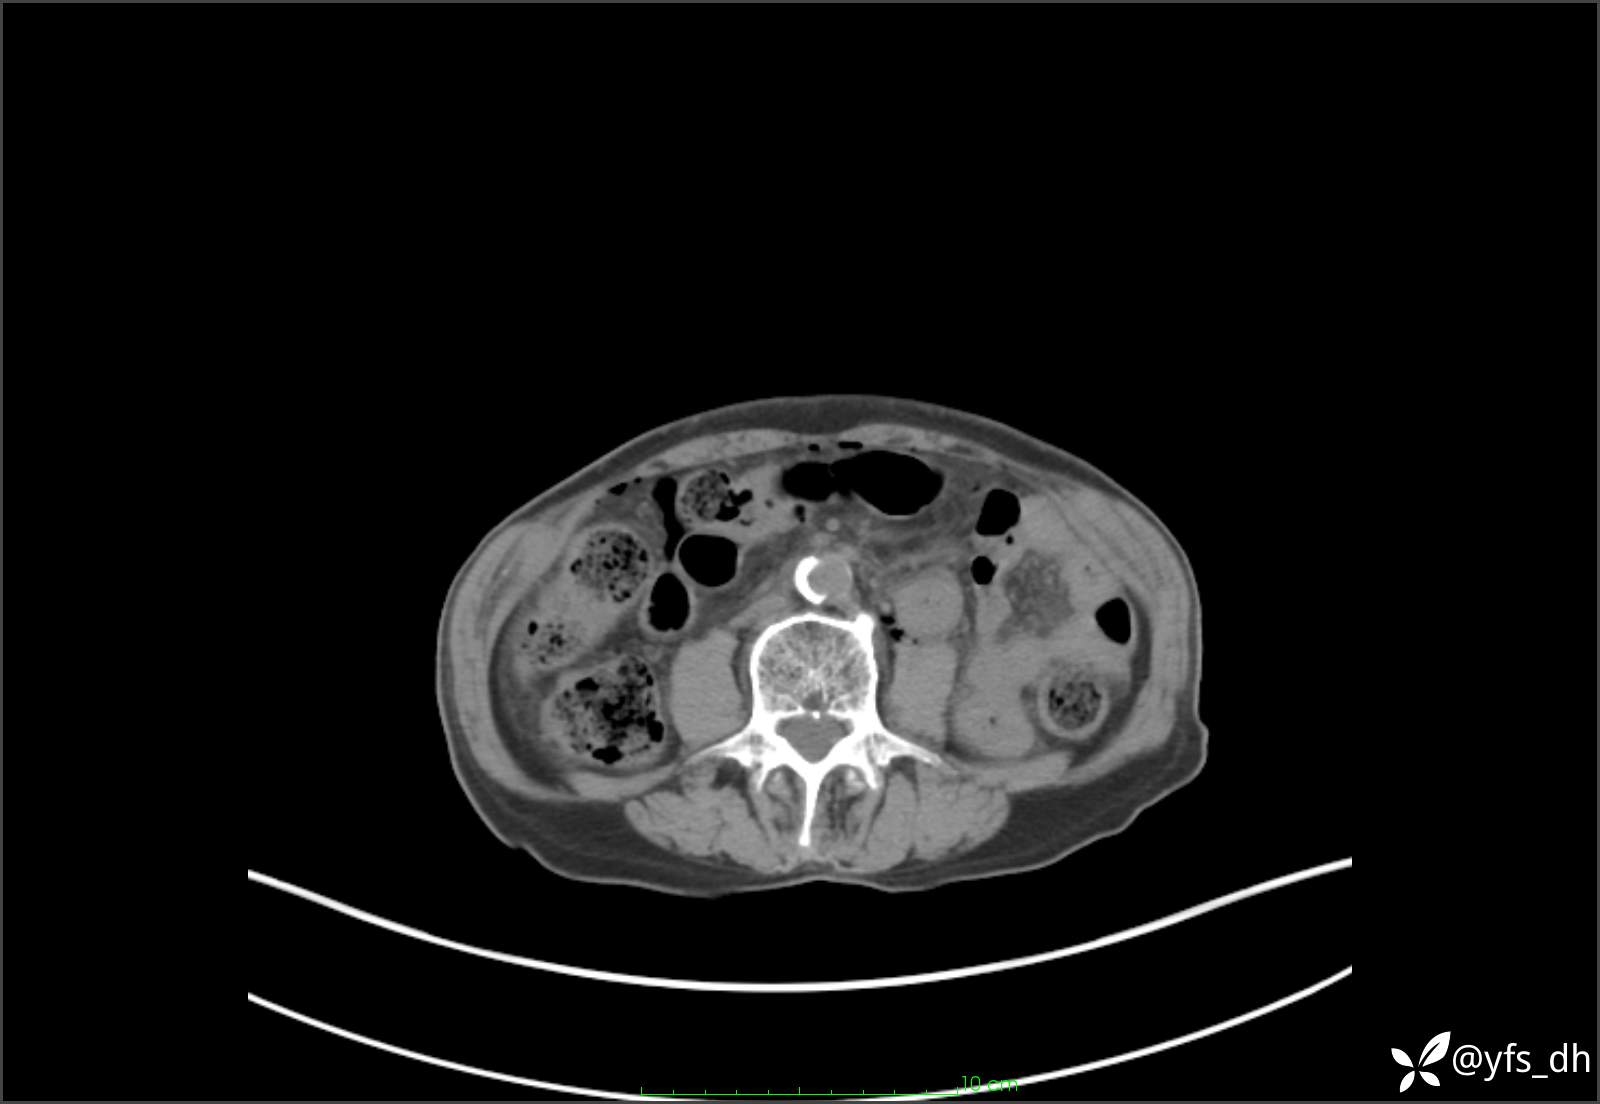

1.简要病史:患者4天前突发上腹部疼痛不适,但可以忍受。3小时前饭后突然加重,不能忍受后就诊。

2.简要手术记录:术中见腹盆腔大量肠液及粪便,乙状结肠中下段见一约3cm的破口。